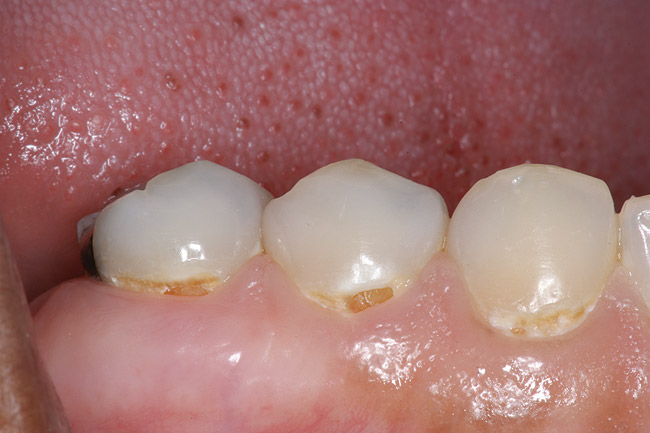

Fig. 4 Defective margins. Mandibular first molar with an amalgam restoration with defective margins.

Figure 4  Defective margins. Mandibular first molar with an amalgam restoration with defective margins.

Figure 4

Replacement of existing restorations is responsible for 75% of all operative dentistry.15,19 The reasons for placement and replacement of restorations of direct restorative materials include: primary caries (Figure 1 and Figure 2); recurrent caries (Figure 3); poor margins (Figure 4 and Figure 5); restoration fracture (Figure 6 and Figure 7); tooth fracture (Figure 8); esthetics (Figure 9); non-carious tooth structure lost (attrition, abrasion, abfraction, erosion) (Figure 10); and pain/sensitivity.